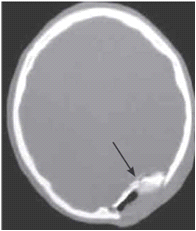

פצוע עם חשד להמטומה אפידורלית חייב לעבור בדיקת טומוגרפיה ממוחשבת של המוח לאישור האבחנה (תצלום 1.16). האבחנה של המטומה אפידורלית מחייבת טיפול נוירו-כירורגי דחוף הכולל ביצוע חורים בגולגולת וניקוז ההמטומה. ניקוז ההמטומה יפחית את הלחץ התוך-גולגולתי וישפר את מצב החולה.

חבלות בקרקפת כוללות המטומות וקרעים. עקב עושר בכלי הדם, קרעים בקרקפת נוטים לדמם מאוד והחולה יכול לאבד דם רב מחבלה שטחית יחסית. הטיפול הראשוני הוא לחץ מקומי כנגד עצם הגולגולת. לחץ מספיק כדי לעצור את הדם. לאחר מכן בחתכים קוויים לאחר הטריה תופרים. חתכים מורכבים דורשים יותר הטריה ולפעמים כיסוי עם מתלי עור של החלק הניזוק. שברים בגולגולות, במיוחד שברי דחיסה (Depressed skull fracture), מסוכנים עקב הלחץ או הפגיעה במעטפות המוח או במוח עצמו (איור 5.16).

האבחנה היא קלינית ורנטגנית. במישוש ניתן להרגיש שקע בגולגולת, וב-CT ניתן לראות את השבר בגולגולת (תצלום 3.16). שברי דחיסה השקועים מעבר ל-5 מ"מ מחייבים התערבות כירורגית להוצאתם. יוצאים מהכלל הם אותם שברי דחיסה שממוקמים מעל הסינוסים של הדורה והרמתם עלולה לגרום לקרע של הסינוס ולדימום שקשה לשלוט עליו. שברים מורכבים עם חשיפה של המוח מחייבים התערבות כירורגית מוקדמת (תוך 12 שעות) למניעת התלקחות זיהומים במקום. עד אז יש לחבוש את המקום באופן סטרילי. אין לנסות להוציא חלקים גרמים או גופים זרים מהפצע או לתפור אותו לפני שהחולה מוכנס לחדר ניתוח, העומד מוכן לביצוע פתיחת גולגולת (Craniotomy) במקרה הצורך.